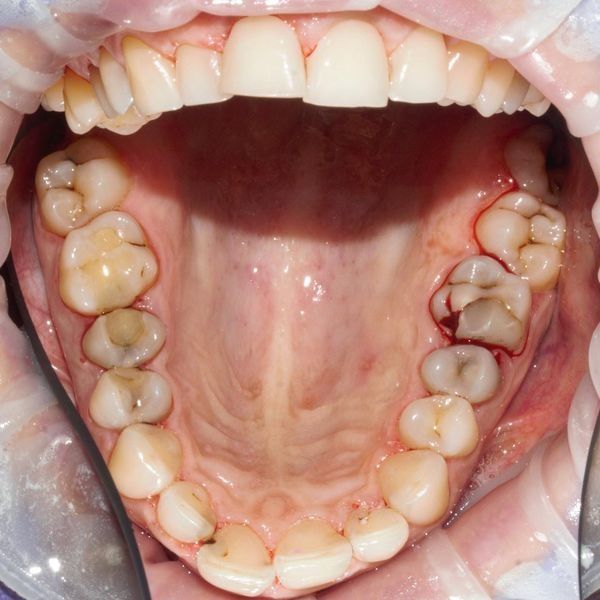

Осмотр жевательных зубов выявил:

- кариес и полости;

- дефектные пломбы с острыми краями;

- разрастание десны;

- зубной налёт и камни.